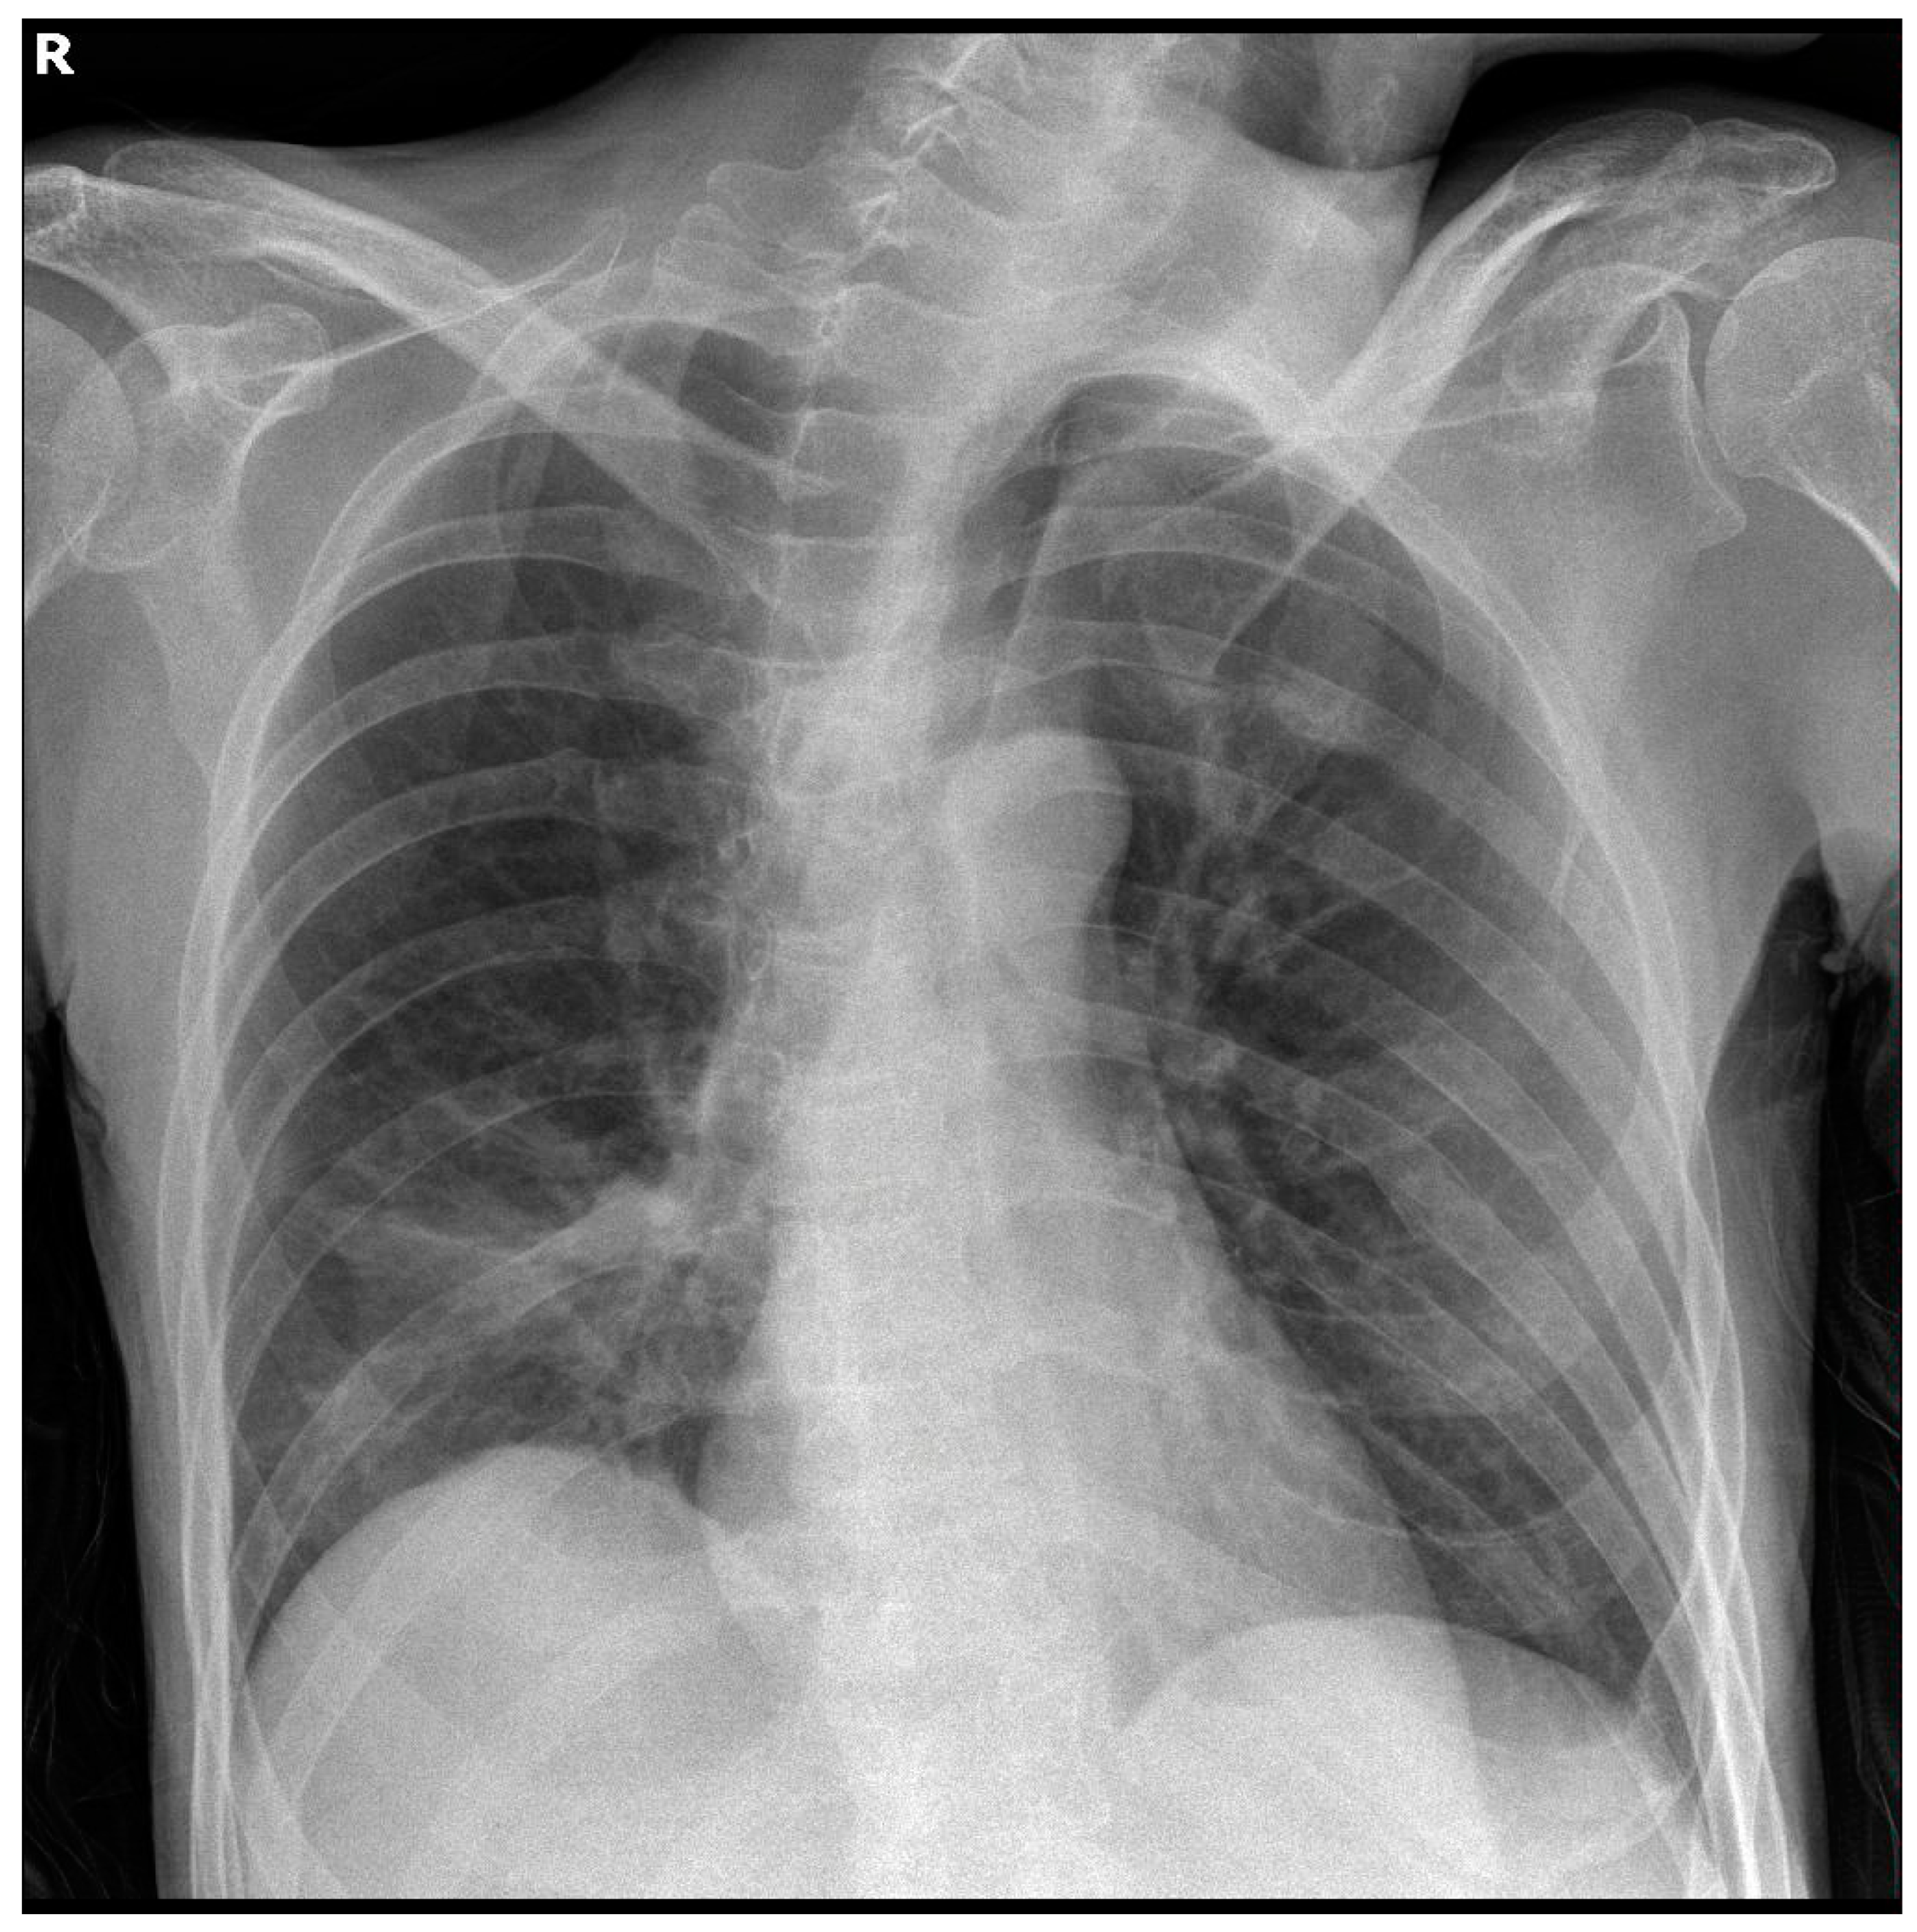

A 45-year-old male of Greek origin was referred to the Emergency Department of the Sotiria Thoracic Diseases General Hospital of Athens due to fever, dyspnea at rest, and productive cough with purulent sputum within the last 24 h. The patient had a previous history of epilepsy and schizophrenia, being catatonically incapacitated, immobilised, and malnourished, while he had also presented multiple aspiration pneumonia episodes in the past. At presentation, clinical examination was remarkable for cachexia, while thoracic auscultation revealed diffuse rhonchi in all lung fields and prolongation of expiration. Laboratory examinations revealed high levels of inflammatory markers, including white blood cell count and C-reactive protein, and normal coagulation studies, including international normalised ratio (INR), prothrombin time (PT), and activated partial thromboplastin time (APTT), as shown in Table 1. Serial chest X-rays throughout hospitalisation showed opacities in the right lower lung field, as shown in Figure 1.

During his hospitalisation, the patient demonstrated extended opacities in the right lung fields, as shown in a repeat chest X-ray, as well as worsening respiratory failure. Chest computed tomography revealed complete atelectasis of the right lung due to occlusion of the right main bronchus by impacted airway secretions and a small ipsilateral pleural effusion. Bedside bronchoscopy was performed to remove the endobronchial secretions, and the right lung eventually re-expanded, as shown in serial chest X-rays. On the 13th day of hospitalisation, the patient manifested relapsing fever and increasing inflammatory markers, while Acinetobacter baumannii was isolated from the bronchial washing culture. Meropenem and vancomycin were thus discontinued, and targeted antibiotic therapy with colistin, tigecycline, and ampicillin/sulbactam was started based on the antibiogram.

Figure 1. Chest imaging of the patient. Chest X-ray showed opacities in the right lower lung field, a finding compatible with aspiration pneumonia.